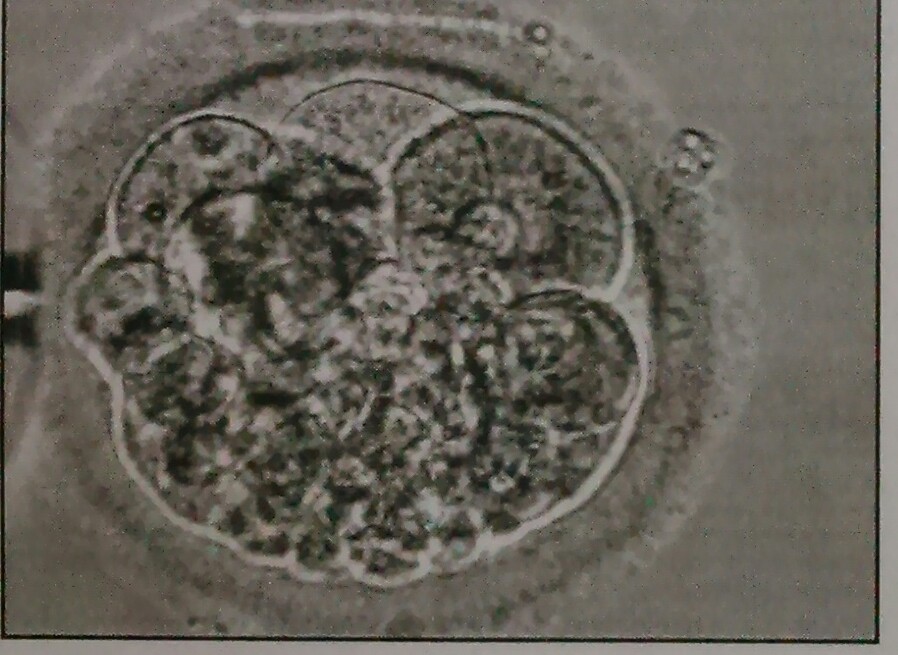

Können sie mir sagen, um welche Qualität es sich hierbei handelt?

Mir wurde nur gesagt, 6-8 zeller und sieht gut aus.

soweit ich es von dem Bild erkennen kann, sehe ich einen 6-Zeller mit relativ gleichmäßigen Unterzellen und einem Anteil an Fragmenten von ca 30%. Die Gesamtqualität würde ich mit gut bis mittel angeben, wobei ich darauf hinweisen möchte, dass so eine Momentaufnahme nur eine sehr begrenzt aussagekräftige Beurteilung zulässt.